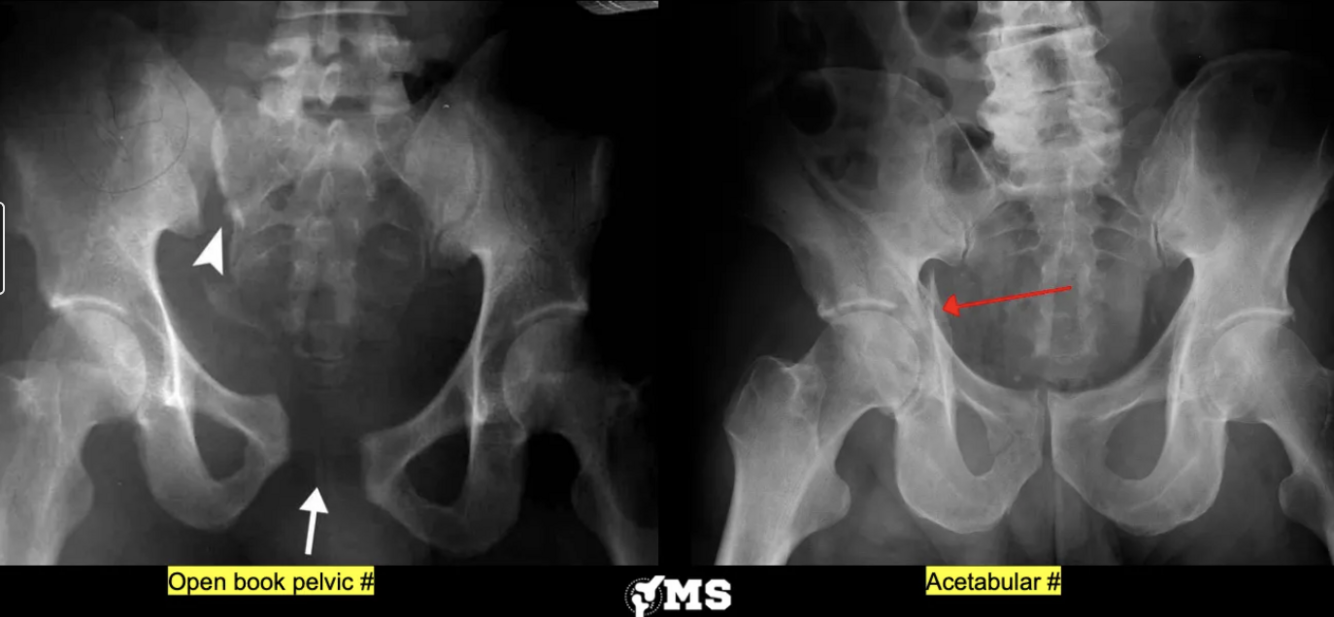

What are the pathologies in this picture?

A